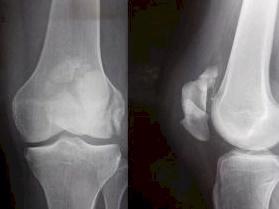

I haqd an Accident, Shattered my Knee into 9 pieces and also broke my thigh and ankle and have now had 4 surgeries, I had to go off work and onto ACC.